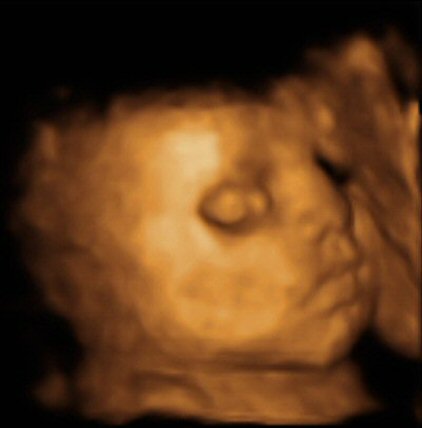

- 29 week 4D scan

- The scan photos shown below are 3D images from the babybond 4D scan at 29 weeks gestation.